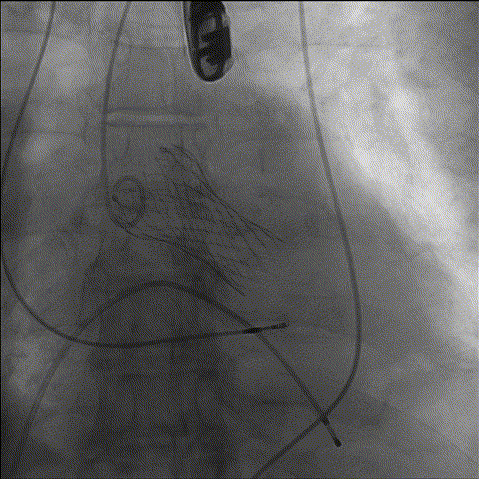

综合各项评估,手术团队采取右侧为主入路,鉴于左冠风险,决定先用10mm球囊,再用22mm球囊预扩,植入Evolut PRO 29mm瓣膜、Cusp Overlap标准6步植入法、20Fr导引鞘。

1、冠脉造影

2、主动脉根部造影

3、预扩